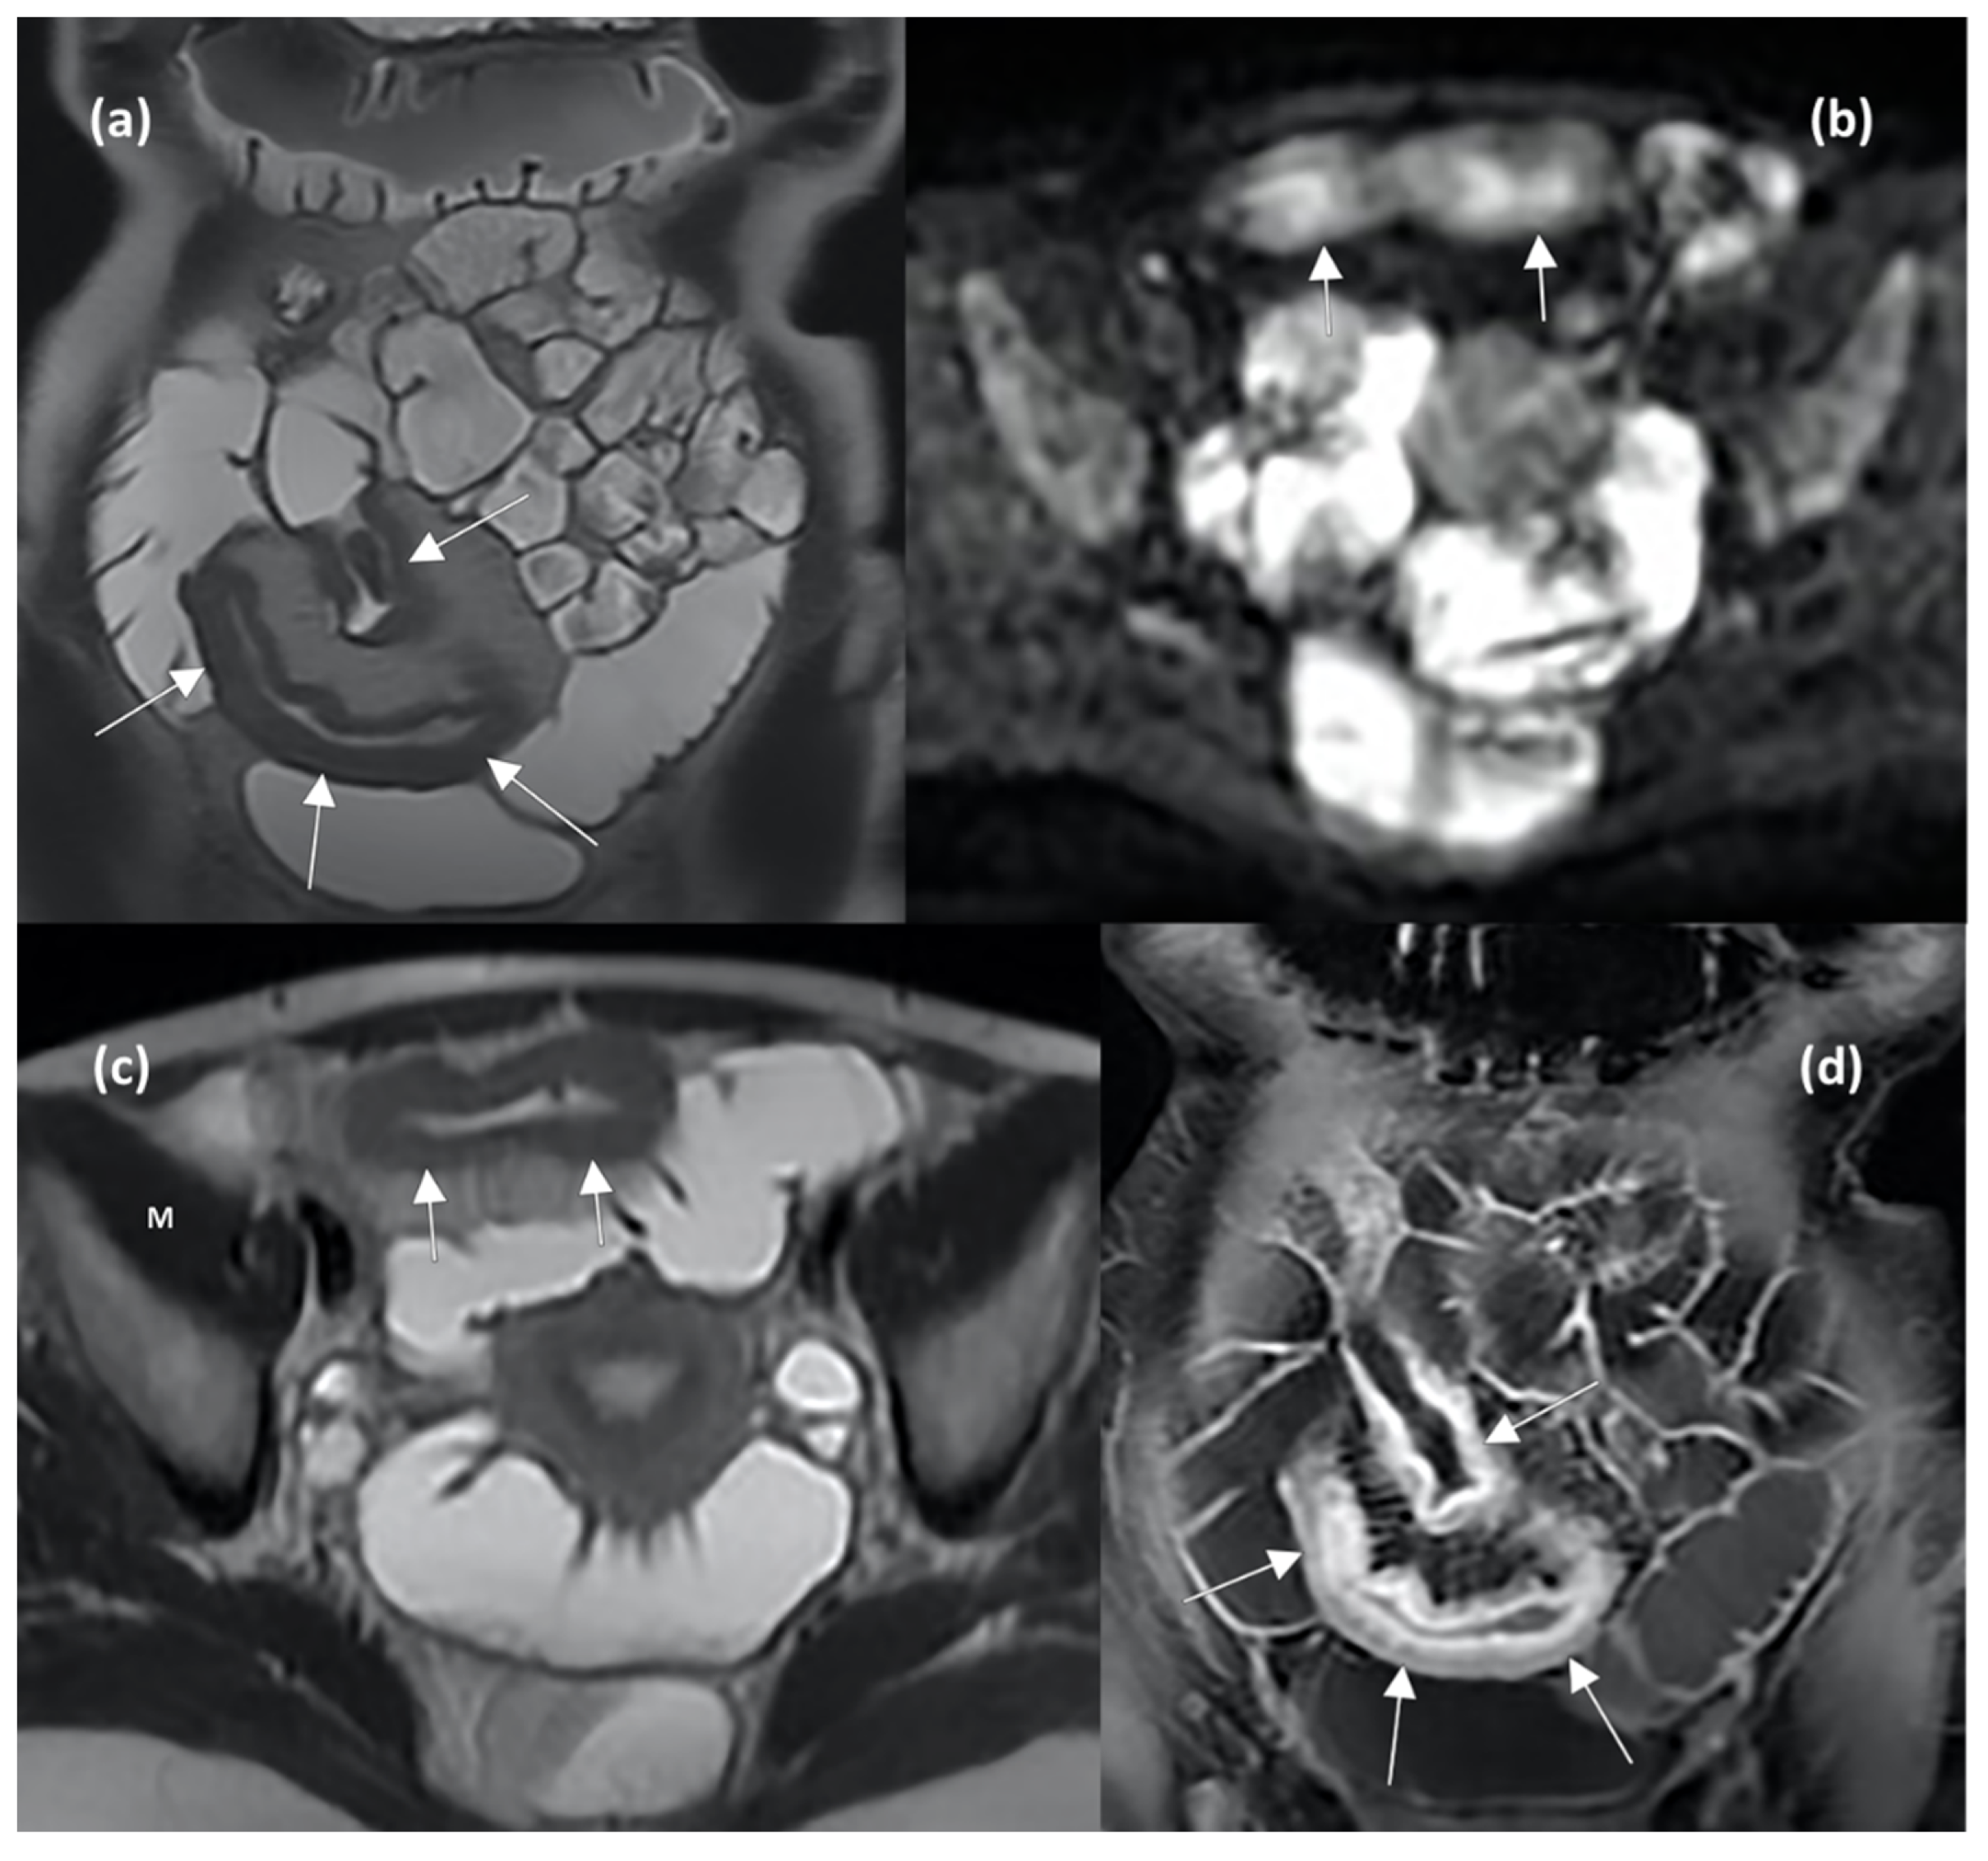

The main MRE and DWI features reflecting active disease and predicting therapeutic response are shown in Figure 4.

Figure 4.

MRE enterography (MRE) images in axial and coronal planes show wall thickening of the distal ileum (arrows in (a,b)), characterized by hyperintense signal compared to muscle (indicating the presence of oedema, letter M in (b)), restricted diffusion in DWI sequence (arrows in (c)), and stratified contrast enhancement after gadolinium injection (arrows in (d)), indicating active inflammation.